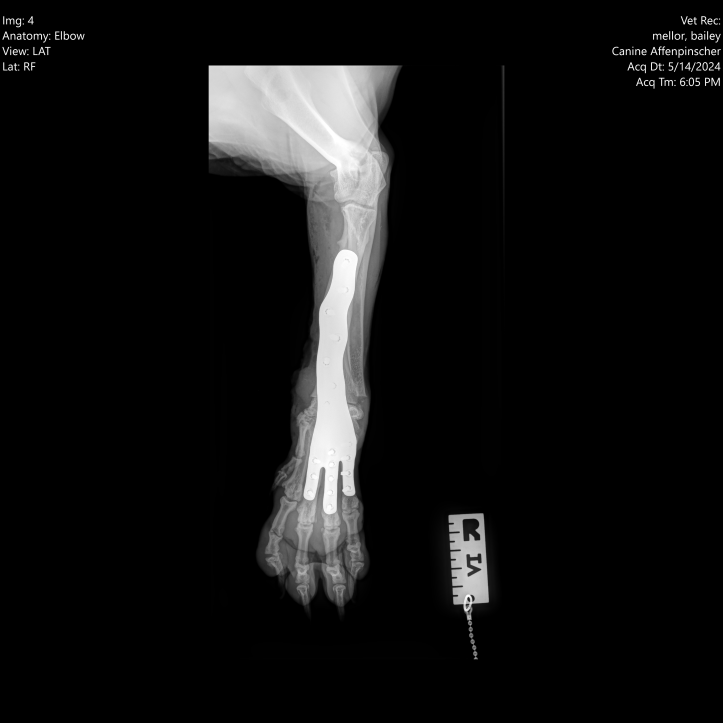

In 2023, Bailey was admitted to Dovecote Veterinary Hospital, where Orthopaedic Specialist James Pratt performed a combined angle correction and partial carpal arthrodesis (PCA) to address the deformity and the resulting arthritis. This advanced surgical procedure involved the use of cutting-edge technology to ensure precision and effectiveness.

bailey1

James, along with a highly trained surgical team, employed 3D-printed guides made by Bill Oxley at Vet3D to make precise cuts in the correct direction. These guides were tailored specifically for Bailey's unique anatomical structure, ensuring optimal accuracy. Following the bone cuts, a custom 3D-printed plate was used to align the bones correctly while the carpal joints fused. This approach not only facilitated the proper alignment of Bailey's carpus, but also promoted successful joint fusion, ultimately relieving the pain associated with osteoarthritis.